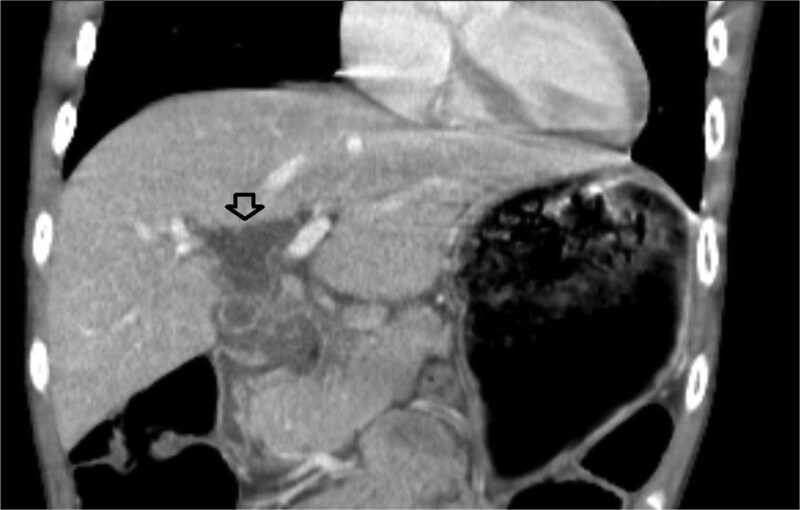

儿童幽门螺杆菌感染只占疾病的一小部分,而在发达国家,这一比例正在下降。典型的表现在文献中有很好的描述。我们报告了一位15岁的男性,他表现为黄疸、贫血、尿色深和腹痛,并被发现有幽门螺旋杆菌感染引起的十二指肠溃疡继发梗阻性黄疸。梗阻性黄疸是很少报道的十二指肠溃疡并发症,特别是在儿童。本报告回顾幽门螺杆菌感染,概述消化性溃疡疾病的并发症,并说明梗阻性黄疸作为儿童十二指肠溃疡的罕见表现。

Pediatric Helicobacter pylori infection represents a small proportion of disease that is otherwise decreasing in the developed world. Typical presentations have been well-described in the literature. We report a 15-year-old male who presented with jaundice, anemia, dark urine, and poorly characterized abdominal pain and was found to have obstructive jaundice secondary to a duodenal ulcer resulting from H. pylori infection. Obstructive jaundice is a seldom reported complication of duodenal ulcer, particularly in children. This report reviews H. pylori infection, outlines complications of peptic ulcer disease, and illustrates the rarity of obstructive jaundice as a presenting sign of duodenal ulcer in children.